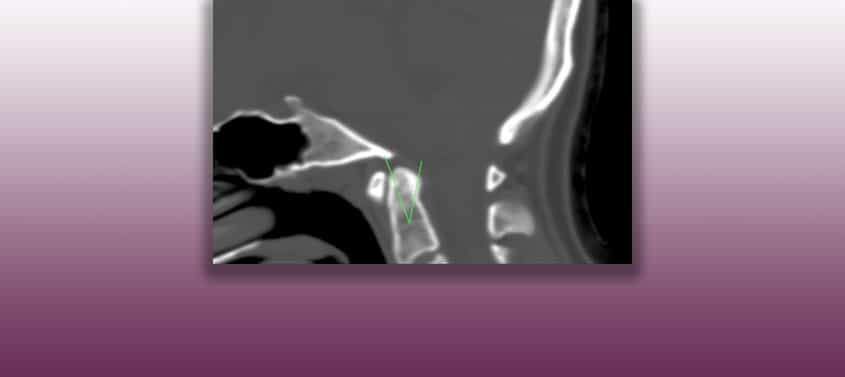

Dorsalverlagerung des Dens axis

Last update: 29/05/2023, Dr. med. Miguel B. Royo Salvador, Arztnummer: 10389. Neurochirurg und Neurologe. Definition Die Odontoid-Retroflexion (OR) oder Dorsalverlagerung des Dens axis ist eine Fehlbildung des oberen Teils der Halswirbelsäule, die in einer Rückwärtsneigung des Odontoidfortsatzes besteht und die angrenzenden Nervenstrukturen verdrängt und zusammendrückt. Es handelt sich um eine Einstülpung der Spitze des Odontoidfortsatzes, […]